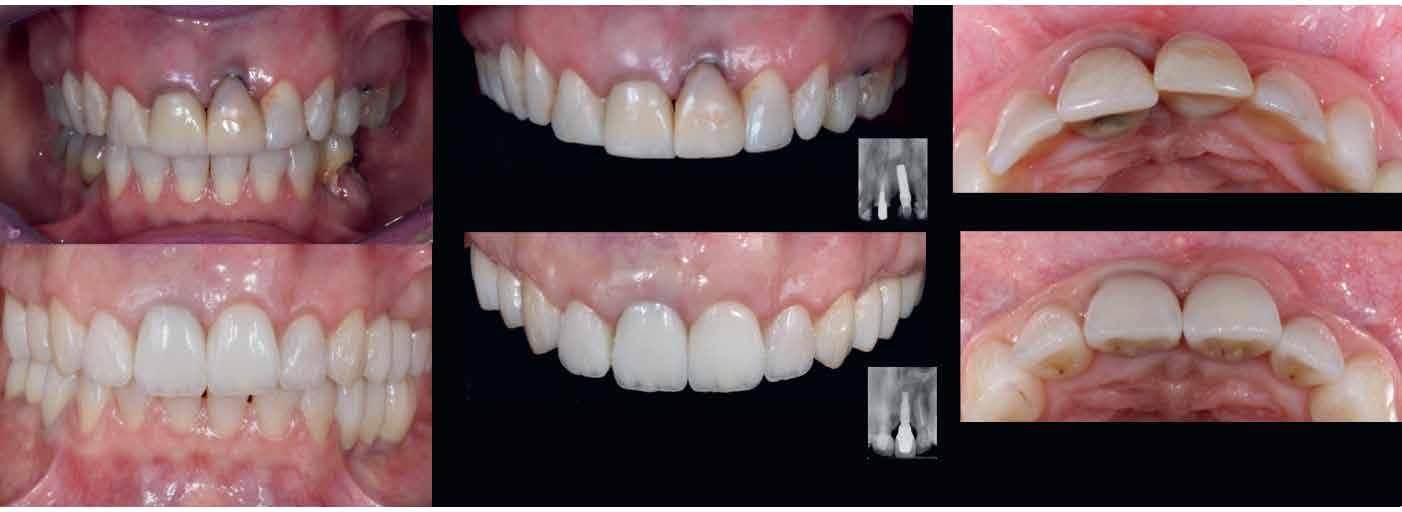

A rendelésünkön egy 34 éves latin-amerikai nőbeteg azzal a panasszal jelentkezett, hogy a fogait „túl rövidnek” találja, és ezen felül a mosolyával sem volt megelégedve. Az anamnézisfelvétel alapján egészséges volt, elmondása szerint rendszeresen járt orvoshoz. Öt évvel korábban néhány hátsó fogát restaurálták. Páciensünk szájhigiénéje megfelelő volt,

a fogait rendszeresen ápolta. House klasszifikációja szerint, amely a pácienseket a fogászati kezelésekhez való attitűdjük szerint négy csoportba sorolja, a páciensünk a szabálykövető csoportba tartozott.

Az előzetes állapotfelmérést és a kezelés megtervezését követően a fogakat minimál invazív módon preparáltuk (1. a-b ábrák), majd az előkészített fogak ínybarázdáiba fonalbehelyező eszköz segítségével (113 Serrated Gingival Cord Packer, Hu-Friedy, Chicago, Illinois) teflonszalagot helyeztünk (Loctite Thread Seal Tape, Henkel Loctite Corp., Egyesült Államok), (1. c ábra). A hagyományos retrakciós fonalak helyett, a rugalmasságuk miatt előnyösebbnek tartjuk a teflonszalagok használatát. A kofferdámot (Dental Dam, Nic Tone, Bukarest, Románia) az előkészített fogakon kívül, az azoktól disztálisan elhelyezkedő egy-egy fognak megfelelően is perforáltuk.

Mivel a felső fogív első kisőrlőfogtól ellenoldali első kisőrlőfogig terjedő részét terveztük kerámia héjak segítségével ellátni (14-24), ezért az izolálást ugyanezen fogív második kisőrlőfogtól második kisőrlőfogig terjedő részére (15-25) helyeztük fel (2. a ábra). A kofferdám rögzítését a második kisőrlőfogakra helyezett kapcsok segítségével (Rubber Dam Clamps #2, Hu-Friedy, Chicago, Illinois, Egyesült Államok) biztosítottuk (2. b ábra). Ezt követően a gumilepedő fogakat körülvevő szélét kézi fonalbehelyező eszközzel és finom levegőáramlattal az ínybarázdákba forgattuk. A folyamat a következőképpen zajlott: a kézi eszközzel a kofferdámot a fognyaknak megfelelően finoman a szulkusz irányába fordítjuk, majd az eszköz végét a fognyaknak megfelelően vezetjük, miközben a lepedőt a puszterből jövő levegő segítsé-

A gumilepedő és a kiválasztott kapcsok (A). A kisőrlőfogakra helyezett kapcsok stabilizálják a kofferdámot (B). A gumilepedő ínybarázdákba történő beforgatása fonalbehelyező eszköz és levegőáramlat segítségével (C). Közvetlenül a héjak felhelyezése előtt a frontfogakra helyezett kapcsok (D).

ábra: A kapcsok eltávolítása és a kismetszőfogakra készült héjak beragasztása. A kapcsok nagymetszőfogakról történő eltávolítása (A). A kapcsok eltávolítása után látható állapot (B). A nagymetszőfogak és a szemfogak teflonszalaggal történő izolálása (C). A kismetszőfogak ínykapcsokkal történő kiegészítő izolálása (D). A héjak átadása után látható állapot (E).

gével finoman az ínybarázdába fordítjuk (2. c ábra). Azokra a fogakra, amelyekre aktuálisan héjakat akartunk helyezni, ezen felül kiegészítő kapcsokat is helyeztünk (Hygenic Brinker Clamp #B4, Coltene/Whaledent Inc., Cuyahoga Falls, Ohio, Egyesült Államok), (2. d ábra) Ebben a stádiumban érdemes a héjakat még bármilyen ragasztóanyag vagy próbapaszta nélkül a helyükre illeszteni (dry tryin). Erre azért volt szükség, hogy még a tényleges ragasztási folyamat megkezdése előtt ellenőrizni tudjuk a restaurátum és a fog pontos illeszkedését, valamint a széli záródási vonalhoz való akadálytalan hozzáférést (3. a ábra). Ideális esetben a héjak felhelyezését párosával, a középvonaltól disztál felé haladva végezzük. Ennek megfelelően a jobb (1.1) és bal felső nagymetszőfogakra (2.1) kapcsokat helyeztünk, majd a szomszédos fogakat teflonszalag segítségével izoláltuk. Ezt követően az 1.1-es és 2.1-es fogak héjak elhorgonyzására szolgáló felszíneit 32%os foszforsavval (Uni-Etch w/BAC, Bisco Dental, Schaumburg, Illinois, Egyesült Államok) 30 másodpercen keresztül kondicionáltuk. Ez után a felszínek vízzel történő lemosása és óvatosan

leszárítása következett (3. b ábra). A fogfelszínek előkészítésének utolsó lépéseként a primert és az adhezívet (OptiBond FL, Kerr Dental Orange, Kalifornia, Egyesült Államok) a gyártói javaslatnak megfelelően a felszínekre applikáltuk, majd 20 másodpercen keresztül polimerizációs lámpával világítottuk (Valo LED Curing Light, Ultradent Products Inc., South Jordan, Utah). Az 1.1-es és 2.1-es fogakat borító héjak ragasztása során világos színű, fényre kötő ragasztócementet (Variolink Esthetic LC, Ivoclar Vivadent, Schaan, Liechtenstein) alkalmaztunk. A ragasztóanyagot először a héjak belső felszínére vittük fel, majd ezeket az előkészített fogfelszínekre helyeztük (3. c ábra). Az approximális felszíneken megjelenő cementfelesleget egy ecset (Profi Natural Bristle Brush, Renfert, Hilzingen, Németország) és fogselyem (Oral-B Glide Pro-Health Deep Clean Floss, Procter & Gamble, Cincinnati, Ohio, Egyesült Államok) segítségével még a ragasztóanyag megvilágítása előtt eltávolítottuk. A megvilágítás során a különböző fogfelszíneket (labiális, meziális, disztális és incizális) 20-20 másodpercen keresztül világítottuk meg (3. d ábra)

Ezt követően a felső nagymetszőkre helyezett kapcsokat

5. ábra: A cementfelesleg eltávolítása. A cementfelesleg fognyakról történő eltávolítása (A). A cementfelesleg approximális területekről történő eltávolítása (B). A cementfelesleg penge használatával történő eltávolítása (C).

egy kapocsfeszítő (4 Rubber Dam Clamp Forceps, Hu-Friedy, Chicago, Illinois, Egyesült Államok) segítségével eltávolítottuk (4. a-b ábrák). Ezután a kismetszőfogak előkészítése következett. Még a kapcsok felhelyezése előtt a szomszédos fogakat, azaz a jobb és bal felső szemfogat, valamint a felső nagymetszőfogakat (1.3, 1.1, 2.1, 2.3) teflonszalaggal izoláltuk (4.c. ábra). Ezután a korábban részletezett ragasztási protokollt követve a kismetszőfogakra készített héjakat beragasztottuk. Ezt a folyamatot a felső szemfogak, és végül az első kisőrlőfogak esetében is megismételtük (4. d-e. ábrák)

A fognyaki területen és a fogközökben megjelenő cementfelesleget egy speciális kézi kürett (LM-Arte Eccesso, Planmeca, Helsinki, Finnország), approximális polírszalag és egy #12-es szikepenge (Surgical Scalpel Blade No. 12., Salvin Dental Specialties, Charlotte, Észak-Karolina, Egyesült Államok) segítségével távolítottuk el (5. a–c. ábrák)

Az oxigén inhibíciós réteg kialakulásának elkerülése érdekében a kerámiafelszíneket glicerin géllel (Liquid Strip, Ivoclar Vivadent, Schaan, Liechtenstein) borítottuk, majd ezeket a felszíneket ismét 20-20 másodpercen keresztül világítottuk. A végeredmény megfelelt a páciens esztétikai igényeinek (6. a. ábra). Az átadott restaurátumok épségének megőrzése érdekében, a páciens számára éjszakai fogvédő sín készült. Az ötéves kontroll alkalmával megállapítottuk, hogy az elvégzett kezelésünk továbbra is sikeresnek tekinthető (6. b. ábra)